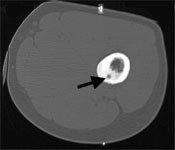

Then the drill is removed but the canula is left inside and the RF-probe is advanced through the canula into the nidus. The RF-probe is a straight rigid electrode with an outer diameter of 1 mm and it is insulated throughout its extent except the terminal 10 mm. The electrode is positioned in the center of the lesion to coagulate a sphere of tissue of 1cm diameter with the tip of the electrode at the center.

The RF-probe was placed in the nidus of the lesion (arrow).